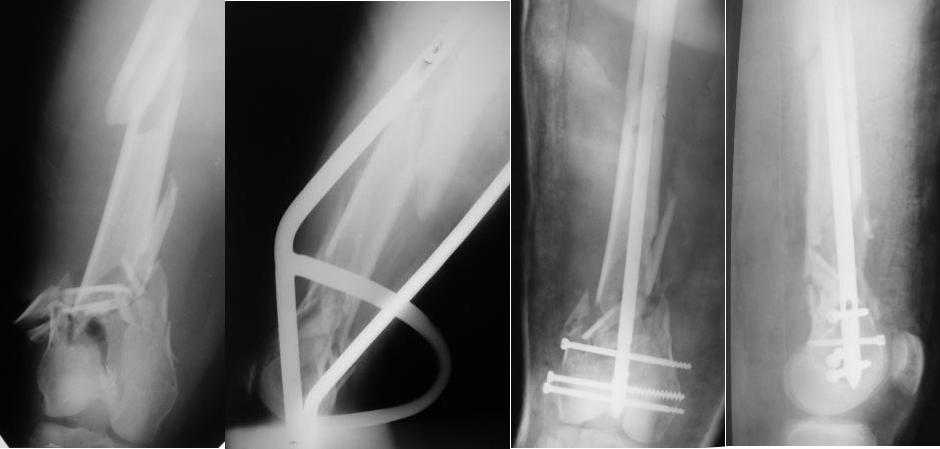

Чтобы больной не смог сгибать колено, выстоять в сустав железо должно побольше значительно, чем на 1 мм. В приложении снимок с выстоянием ммм на 3, видна и функция колена. Хотя клиника импинджмента была, но даже не на один восклицательный знак. После удаления стержня проблемы и вовсе рассосались.

Это результат через полгода. К сожалению, пациент больше не приезжал на контрольный осмотр.